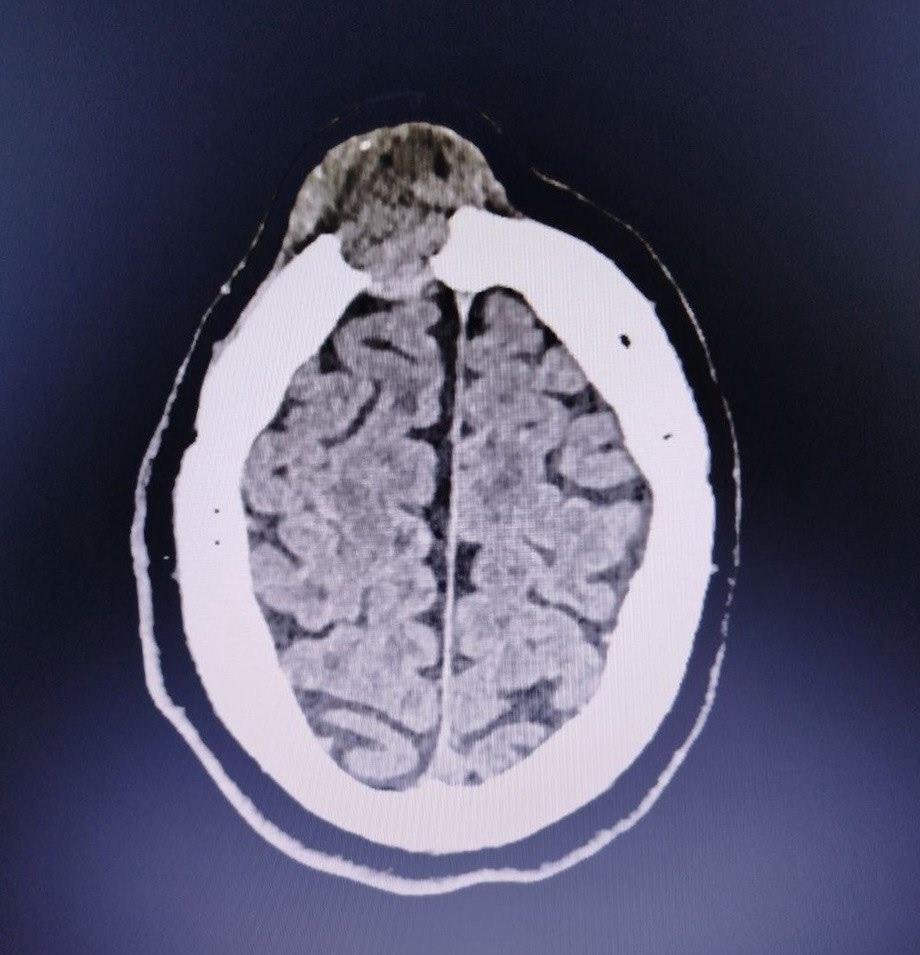

Компьютерная томография показала, что шишка на лбу пациента является опухолью головного мозга.

Обследование с помощью компьютерной томографии выявило опухоль головного мозга. Новообразование уже начало разрушать лобную кость черепа.